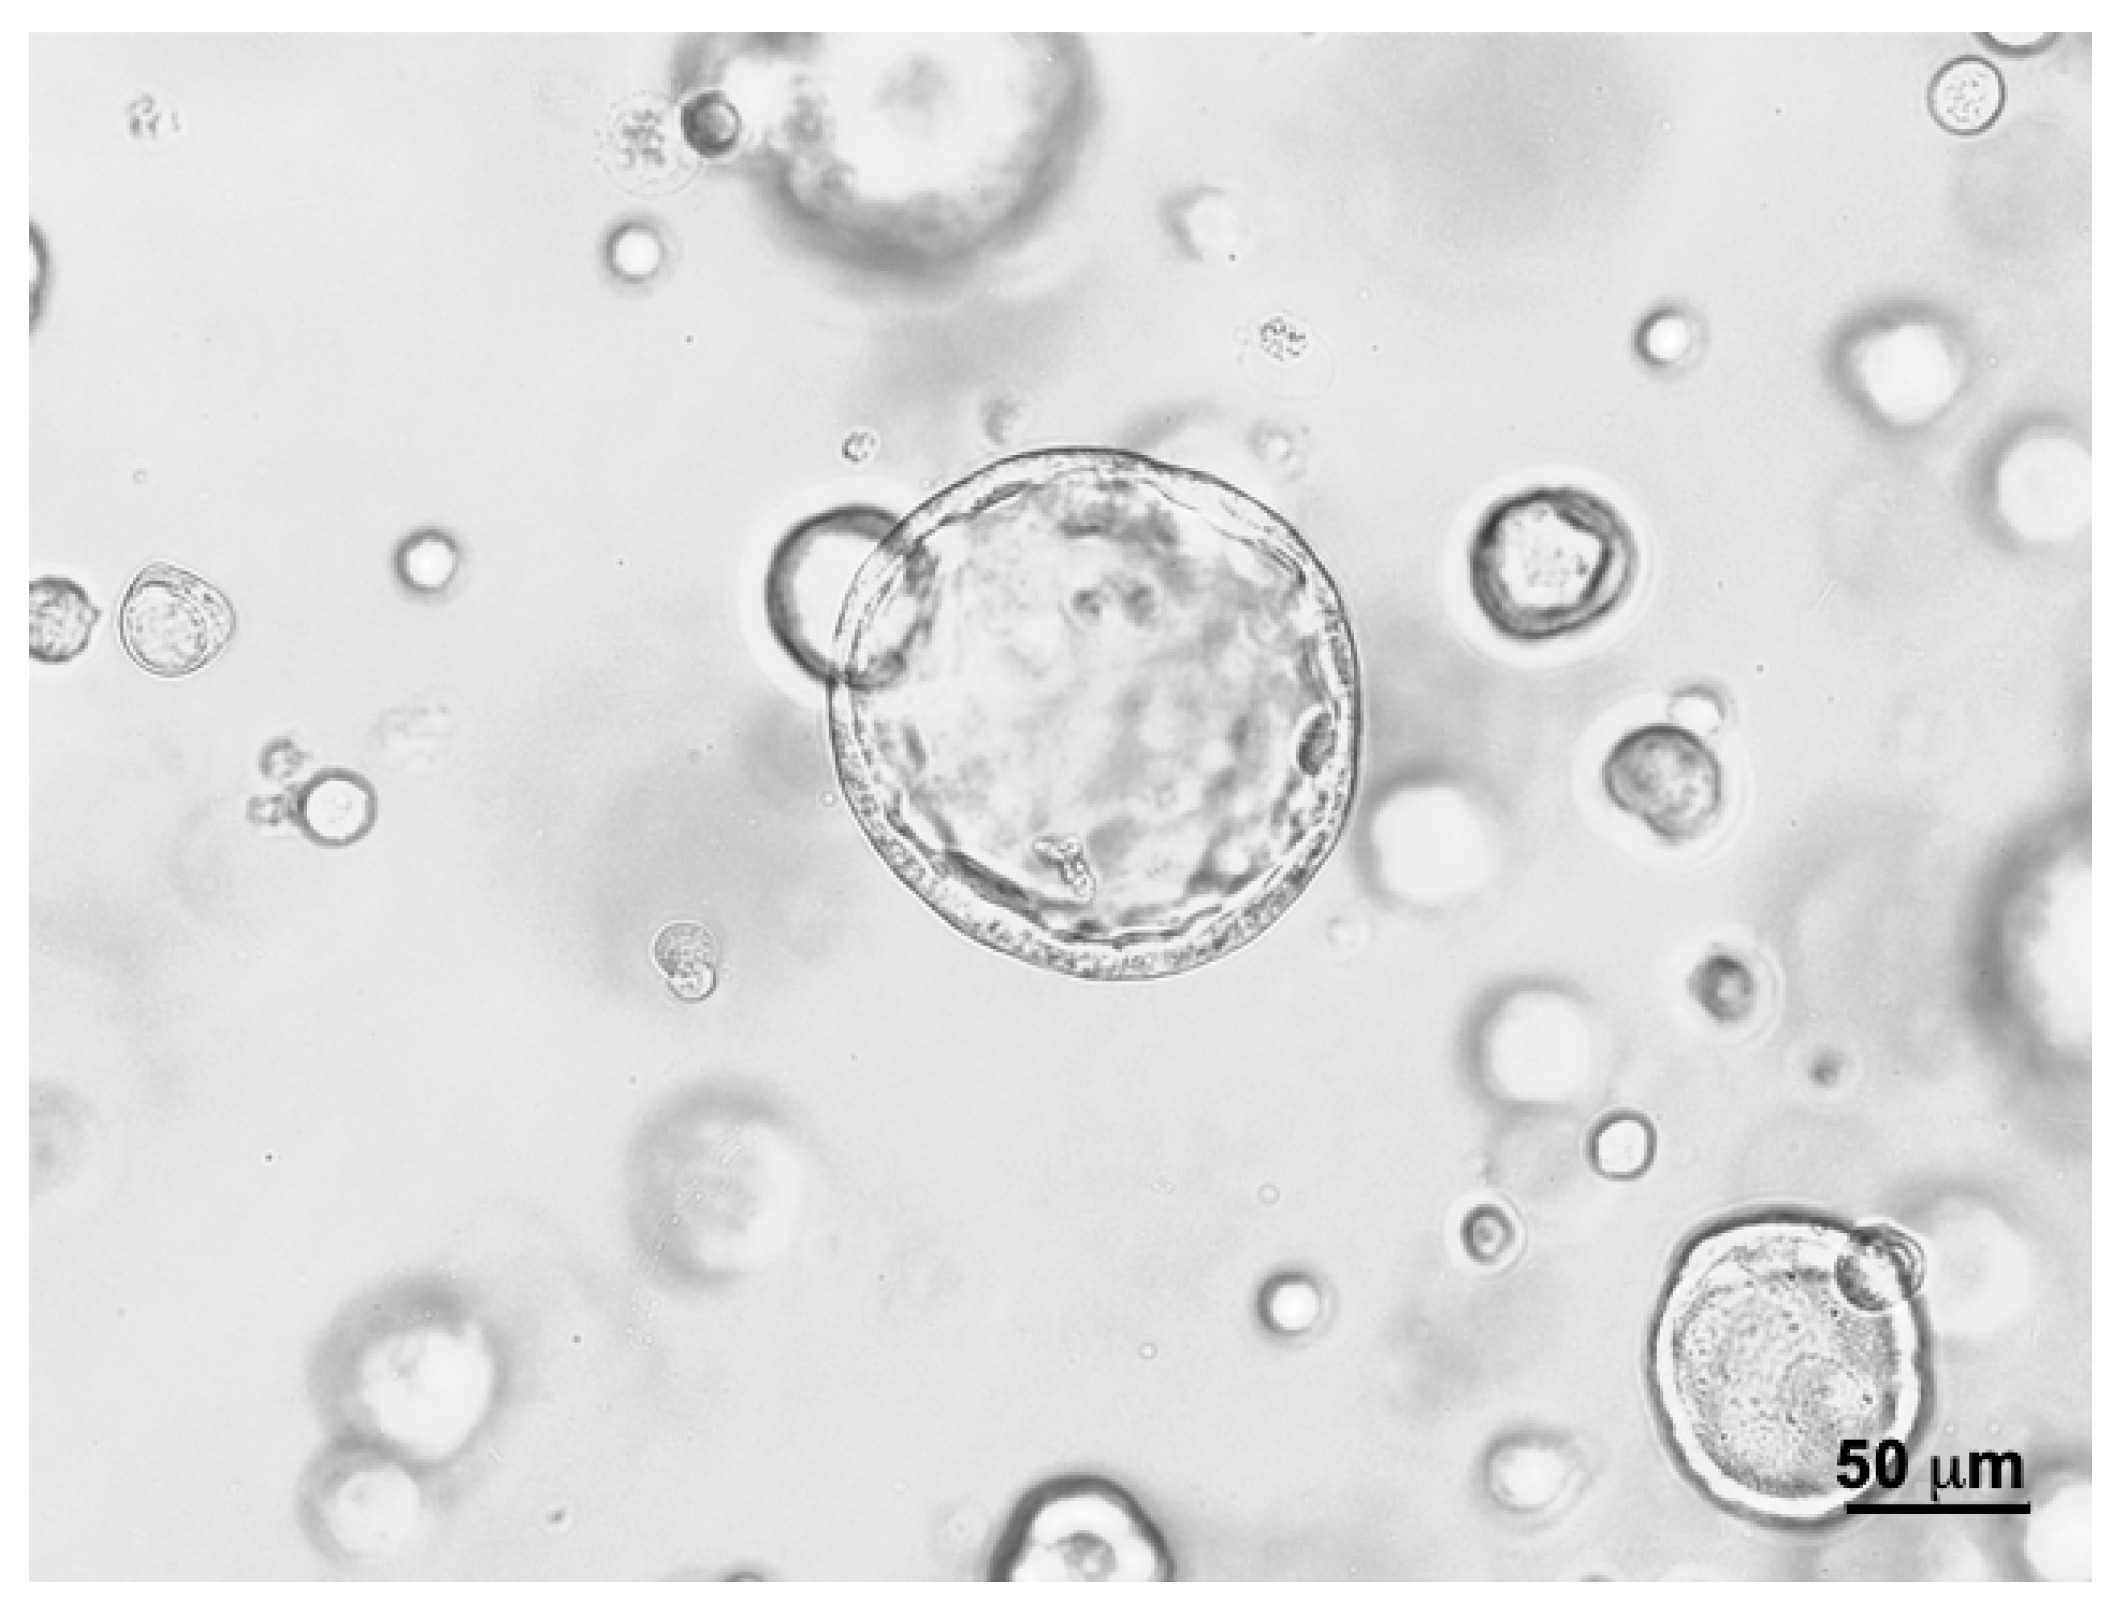

3.1. Optimizing Scaffold Concentrations for Bladder Cancer Cell Cultures

3.2. Effects of Basement Membrane Extract- Versus Cellulose-Derived Scaffolds on Urothelial Carcinoma-Derived Organoid BCO#140

3.3. Effects of Basement Membrane Extract- Versus Cellulose-Derived Scaffolds on Urine-Derived Organoid UCO#33